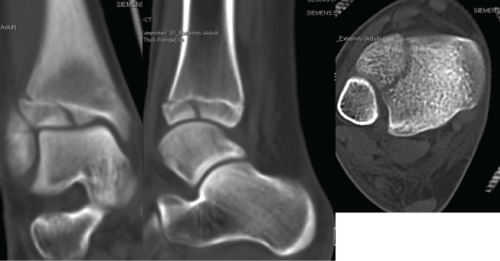

Posterior malleolus fractures are relatively common within the setting of ankle fractures, the most common of which are trimalleolar fracture with an incidence of approximately 7-14.2%. [5,6]. Isolated fractures of the posterolateral tibial lip (Volkmann's Triangle) are rare, with an estimated incidence of 0.5-1% [6,8,9]. The most common injury mechanism is SER, which accounts for the posterior inferior tibial fibular ligament avulsion fracture (Volkmann fracture) or posterior malleolus fractures, which may cause fibular rotational deformity or fibular shifting either anteriorly or posteriorly leading to syndesmotic instability (Figure 8A and Figure 8B). Injury mechanism of isolated Tillaux fracture is most likely PER, which is responsible for anterior inferior tibial fibular ligament avulsion fracture. The AITFL is intact but hinged on Tillaux fragment causing fibular rotation or shifting anteriorly leading to syndesmotic instability (Figure 3). The fibular rotational deformity or sagittal plane shifting is hardly to be assessed on plain radiographs. However, most of those injuries are missed from plain radiographs (Figure 8B).

Figure 8: Axial CT scans in patients with Volkmann fractures combined with other ankle fractures. (a) a 59-year-old female, internal fixation of medial and lateral malleoli fractures without fixation of Volkmann fracture was given. Pre- and postoperative plain radiographs did not reveal any syndesmotic instability but postoperative CT scans showed the fibula was shifted anteriorly due to Volkmann fragment which is hinged on PITFL and displaced laterally in posterior part of the syndesmosis causing syndesmotic incongruency and instability; (b) a 17-year-old male, plain radiographs did not reveal any syndesmotic instability; (c) CT scan showed that the Volkmann fragment was displaced posteriorly and medially causing fibular shifting posteriorly and malrotation that was a main cause syndesmotic incongruency.